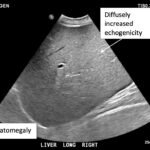

Glycogenic hepatopathy is a rare condition that may be seen in patients with poorly controlled diabetes mellitus. This is a case presentation of a 15-year-old female with type 1 diabetes mellitus who was not fully adherent to her insulin regimen and presented in acute diabetic ketoacidosis. She had the associated symptom of two months of abdominal pain. The patient’s ketoacidosis resolved during her hospitalization with insulin and intravenous fluid management; however, her lactic acid and liver transaminases remained persistently elevated. Abdominal ultrasound was consistent with parenchymal liver disease and a clinical diagnosis of glycogenic hepatopathy was made. Management consisted of tight glucose control. After discharge, the patient was followed closely by pediatric endocrinology and pediatric gastroenterology, and once her glucose was optimized, her transaminitis and lactic acidosis resolved. Although an uncommon condition, it is important to consider glycogenic hepatopathy in diabetic patients with poor glucose control, abdominal pain, transaminitis and lactic acidosis.